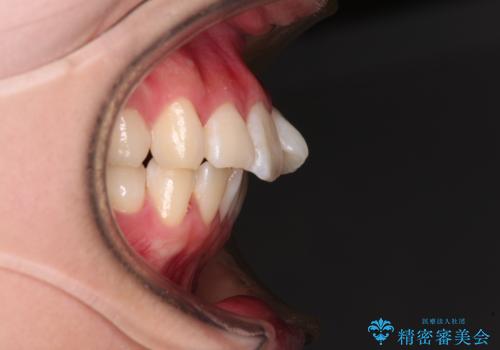

- 前歯がくちばしのように飛び出していることを気にして来院された患者様です。

唇が前方に突出している横顔が気になっているため、上下左右の第一小臼歯4本を抜歯し、ワイヤー装置にて矯正治療を行うこととしました。